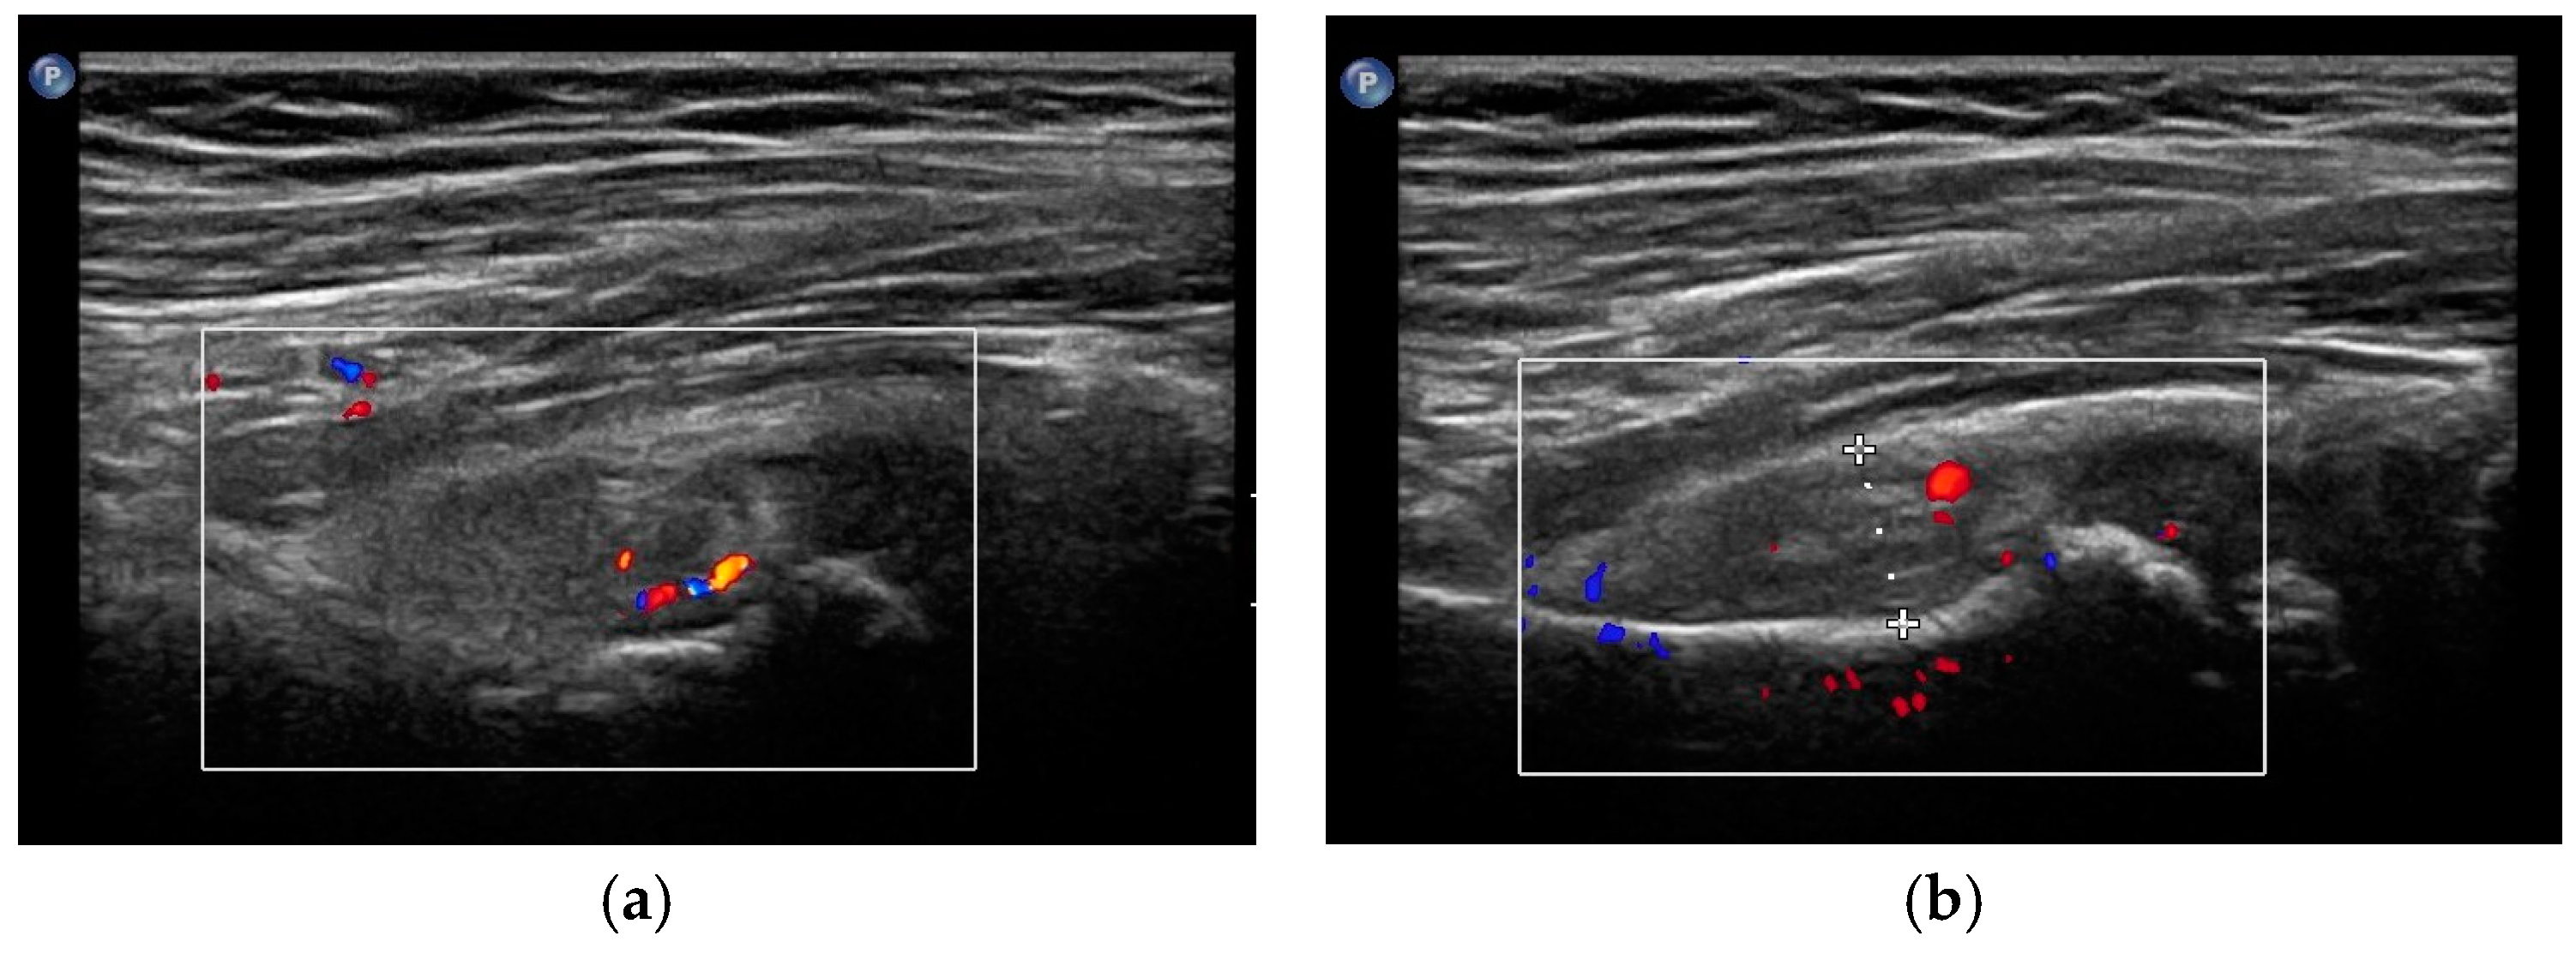

- Maruszczak, K.; Kochman, M.; Madej, T.; Gawda, P. Ultrasound Imaging in Diagnosis and Management of Lower Limb Injuries: A Comprehensive Review. Med. Sci. Monit. 2024, 30, e945413. [Google Scholar] [CrossRef] [PubMed]

- Czyrny, Z. Osgood-Schlatter disease in ultrasound diagnostics—A pictorial essay. Med. Ultrason. 2010, 12, 323–335. [Google Scholar] [PubMed]